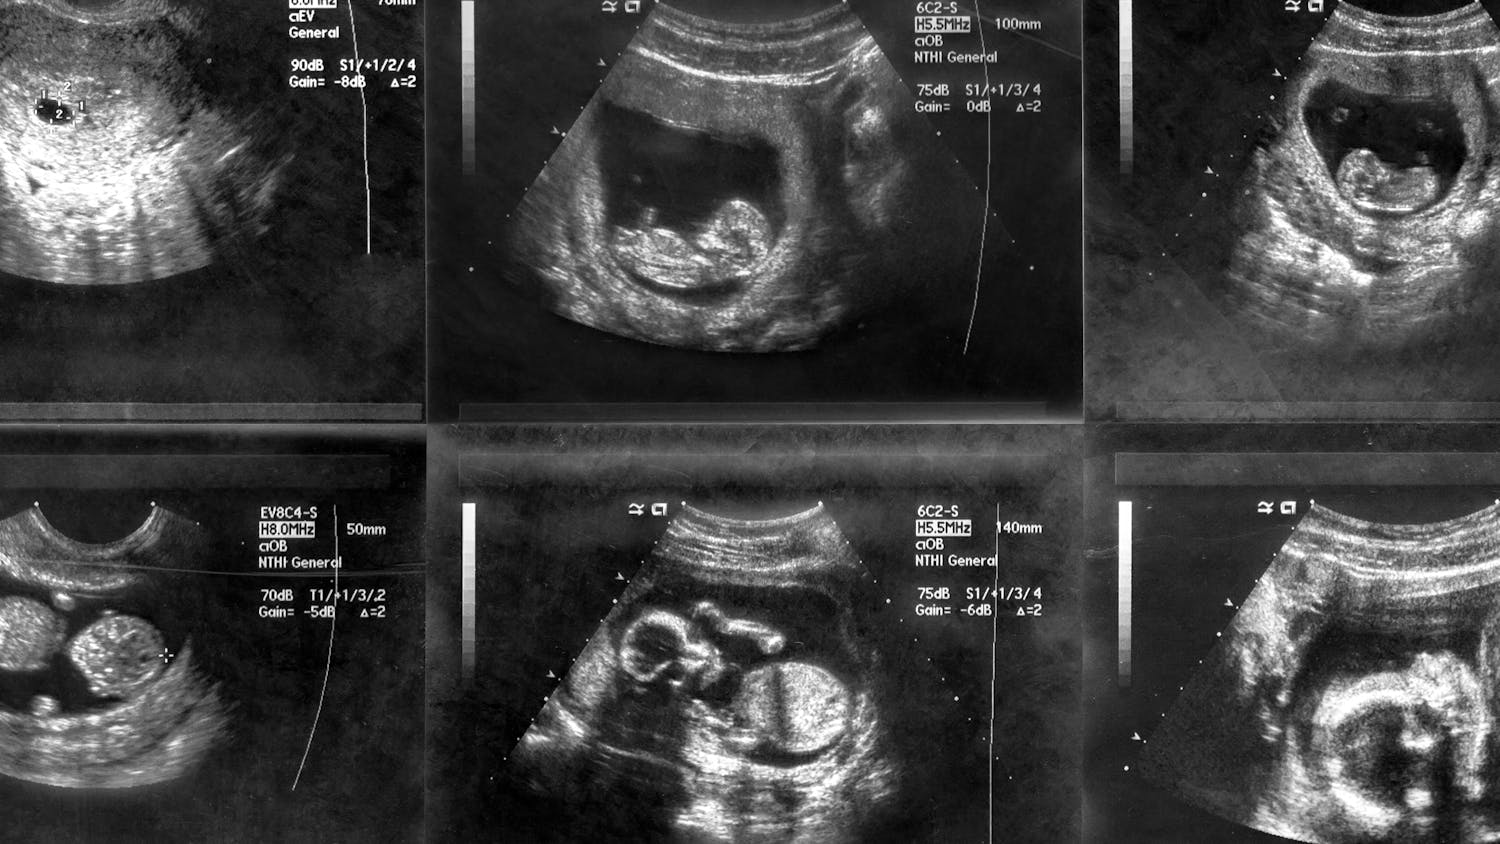

The ultrasound image is of twins at 4 weeks. Nervous system Its development is. Once youre 36 weeks pregnant baby will slow her rapid growth phase and begin to drop into the birth canal.

The babys hair follicles are developed around week 15. Your baby will be much bigger and an ultrasound is done in order to give the following. Web Unfortunately 3D4D ultrasound technology cannot see any hair on the baby however standard 2d black and white ultrasound can usually pick up strands of.

We saw hair in the 2d but the way that a 3d picture is taken you cant see hair. 37 Week Ultrasound 37 Weeks Old Mia Lily Lily Face. Hair on Ultrasound at 37 weeks.